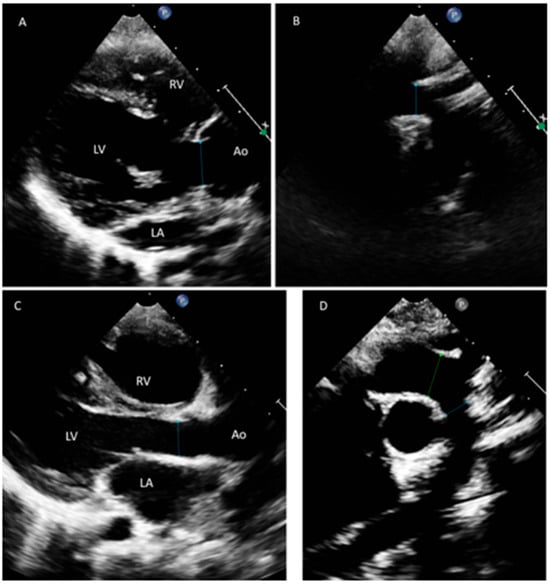

In Family B, the proband patient is a 7-year-old male (II-1, Figure 1B) and the first of a Saudi consanguineous family. The proband was diagnosed with various forms of CHD specifically: a large atrial septal defect (ASDII), a large inlet ventricular septal defect (VSD), a dysplastic and straddling mitral valve, tricuspid valve hypoplasia, and right ventricular hypoplasia. He had undergone several surgical procedures, including pulmonary artery (PA) banding and reconstruction of the main PA with homograft. The proband’s sister (II-2), 21 months old, also had a confirmed diagnosis of CHD. She suffered from depressed cardiac function and moderate common atrioventricular valve regurgitation and was identified with complete atrioventricular septal defect (AVSD) with common atrium, and she had undergone a PA banding surgery (for details, see Supplemental Table S3). Both siblings belong to healthy parents (I-1, I-2) who have no family history of cardiac anomalies. Aortic abnormalities were also investigated in this family, but there was no evidence of abnormal aortic widening or dissection, nor were there any reports of sudden deaths. Both siblings had a normal measurement and z score for the aortic valve and ascending aorta (Figure 2).

Figure 2. Echocardiographic views taken for both Saudi siblings at the parasternal long-axis views (A,C) and suprasternal sagittal views (B,D). Both siblings have normal measurement and z score for the aortic valve and aortic arch. The first sibling has normal aortic valve (A) that measures 1.4cm (z score 0.3) and normal transverse aortic arch 1.2cm (z score 0.3) (B). The other sibling has normal aortic valve (C) that measures 1.0cm (z score -1) and normal transverse aortic arch 0.8cm (z score—1.4) (D). Ao; aorta, LA; left atrium, LV; left ventricle, RV; right ventricle.